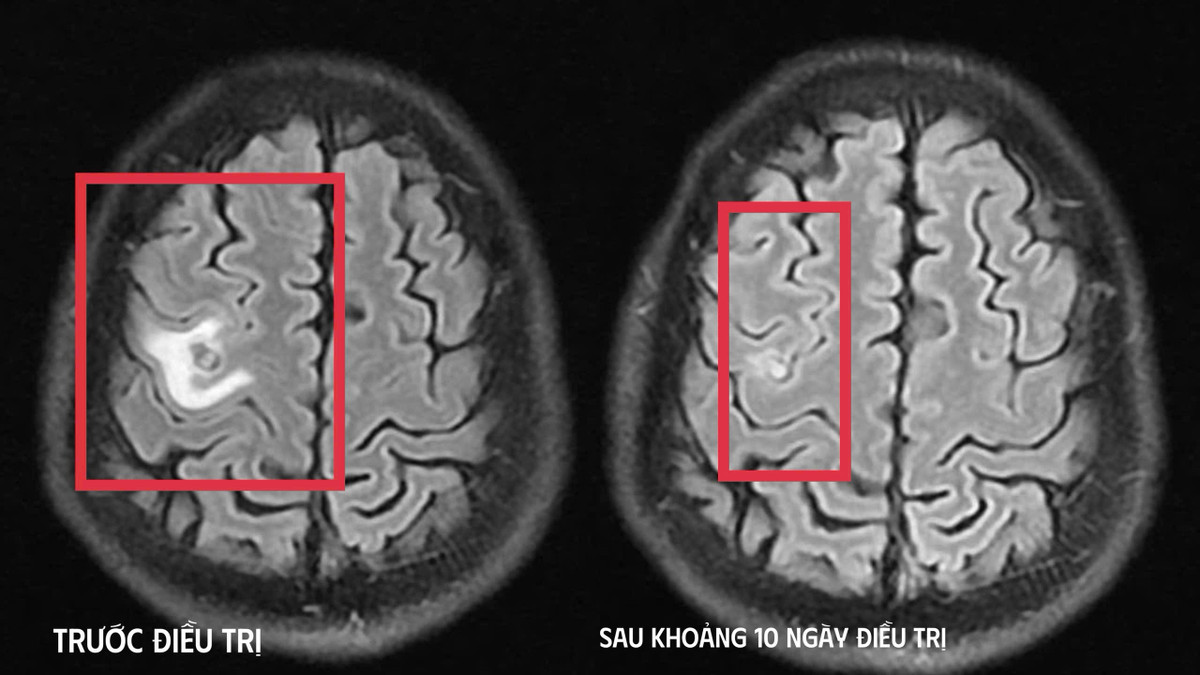

Hình ảnh ổ sán não trước và sau điều trị. Ảnh: BVCC

Chụp cộng hưởng từ sọ não phát hiện một nang nhỏ ở thùy trán trái, kích thước khoảng 11 x 7 mm, kèm phù não nhẹ. Hình ảnh gợi ý tổn thương do ký sinh trùng hơn là u não nguyên phát. Xét nghiệm huyết thanh học kháng thể kháng sán dây chó dương tính, xác định chẩn đoán tổn thương não do ký sinh trùng.

Bệnh nhân được điều trị theo phác đồ, kiểm soát triệu chứng và theo dõi sát diễn biến thần kinh. Sau 10 ngày, tình trạng cải thiện rõ rệt, bệnh nhân hết tê tay, không co giật, đau đầu hay chóng mặt biến mất, toàn trạng ổn định. Bệnh nhân xuất viện và tiếp tục điều trị ngoại trú đủ liệu trình 4 tuần.

Khi tái khám gần một tháng sau, chụp cộng hưởng từ cho thấy nang não thu nhỏ rõ, phù não giảm, không còn dấu hiệu tiến triển, đáp ứng điều trị tốt.